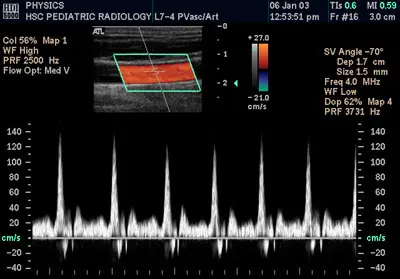

컬러도플러 심장 초음파

컬러도플러 심장초음파 검사(Color Doppler echocardiography)는 혈류의 속도와 방향을 색상으로 표현하여 가시성을 향상 시켜 더욱 생생한 화면을 통해 심장의 상태를 확인할 수 있습니다. 특히 심장 내의 혈행속도 및 역류혈낭 등을 과학적으로 정밀하게 측정할 수 있어 고혈압, 심근경색, 심근질환 등 각종 질환에서 심장 상태의 이상을 빠르고 정확하게 식별할 수 있습니다.